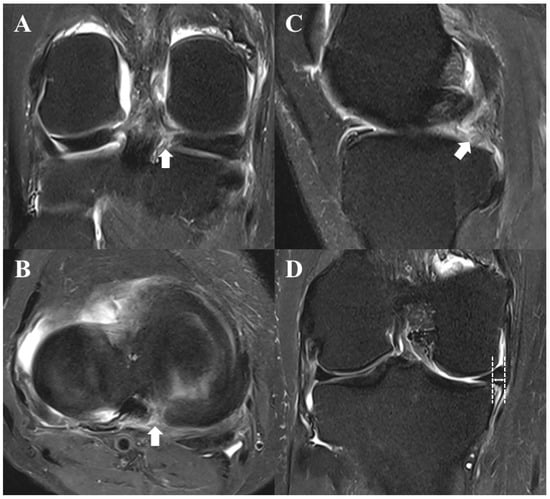

- Choi, S.H.; Bae, S.; Ji, S.K.; Chang, M.J. The MRI findings of meniscal root tear of the medial meniscus: Emphasis on coronal, sagittal and axial images. Knee Surg. Sport. Traumatol. Arthrosc. 2012, 20, 2098–2103. [Google Scholar] [CrossRef] [PubMed]

- Lee, Y.G.; Shim, J.C.; Choi, Y.S.; Kim, J.G.; Lee, G.J.; Kim, H.K. Magnetic resonance imaging findings of surgically proven medial meniscus root tear: Tear configuration and associated knee abnormalities. J. Comput. Assist. Tomogr. 2008, 32, 452–457. [Google Scholar] [CrossRef] [PubMed]